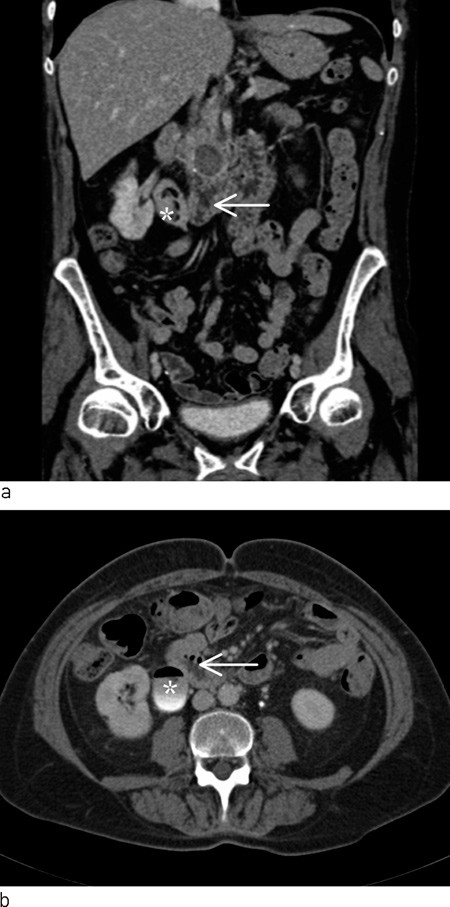

Pasienten ble undersøkt på urologisk poliklinikk tre uker senere. Orienterende blodprøver viste hemoglobin 13,0 g/dl (11,7 – 15,3 g/dl), CRP 3 mg/l (< 10 mg/l), karbamid 9,0  mmol/l (3,0 – 6,5 mmol/l), kreatinin 81 μmol/l (50 – 90 μmol/l). Glukose ble ikke tatt. Ved cystoskopi ble det funnet rikelig med grumsete urin i urinblæren. Det ble ikke påvist konkrementer eller andre fremmedlegemer, og det var ingen patologi i blæreslimhinnen. Cytologi av urin viste normale celler uten atypi. Det ble rekvirert CT urinveier for å undersøke om pasientens hematuri kunne skyldes konkrementer eller prosesser i øvre urinveier eller i relasjon til urinveiene. To uker senere ble det utført CT nyrer og urinveier uten røntgenkontrast og med røntgenkontrast i to faser som viste rikelig med gass i urinblæren og i samlesystemet på høyre side. På høyre side hadde pasienten markert nyrebekken med enkelte fylningsdefekter. Calyces og ureter var slanke. Duodenum lå nært det markerte nyrebekkenet. Venstre nyre og ureter var upåfallende. I caput pancreatis ble det påvist forkalkninger og en cyste med diameter 1,5 cm (fig 1).

Pneumaturi (gass i urinveiene) kan skyldes fistel mellom tarm eller genitalia og urinveiene. Denne tilstanden kan ses som komplikasjon til tykktarmskreft, ved divertikkelsykdom, inflammatorisk tarmsykdom eller etter kirurgisk inngrep i bukhulen (1, 2). Gass i urinveiene kan også ses etter instrumentering i urinveiene eller ved gassdannende bakterier i urinen. Hos denne pasienten hadde vi ingen opplysninger om episoder med divertikkelsykdom, inflammatorisk tarmsykdom eller tidligere kirurgiske inngrep som kunne disponere for en fistel mellom tarm eller genitalia og urinveiene. Cysten i caput pancreatis, som kunne være forenlig med gjennomgått pankreatitt, ble i første omgang oppfattet som et bifunn.